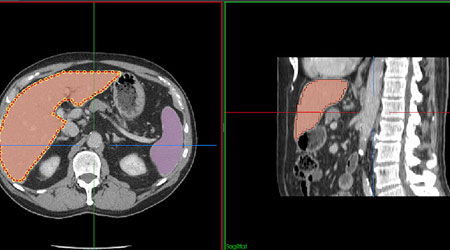

Annotation is a medical imaging technique to highlight areas of interest (often using boxes, circles, or arrows). The word annotation refers to adding metadata to a picture in the related area of digital imaging so that a computer model may be trained to detect particular characteristics. A medical picture annotator often carries out one of two types of annotation.

Segmentation, the first type, involves categorizing individual pixels. Classifying a whole image inside a dataset is the second type. The standard Digital Imaging and Communications in Medicine (DICOM) format is used to edit and encode images. NIfTI is another popular format that creates a 3D picture (as opposed to the single slices format of DICOM). The reader can also change this format, depending on their preferences.

For radiological imaging, the 3D volumes of the patients are manually segmented to separate the different structures in the pictures and enable the processing of the tissue of the systems independently. On the other hand, manual segmentation necessitates arduous and time-consuming work from radiologists.